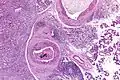

Their histologic appearance is similar to ductal breast carcinoma.

Very low mag.

Intermed. mag.